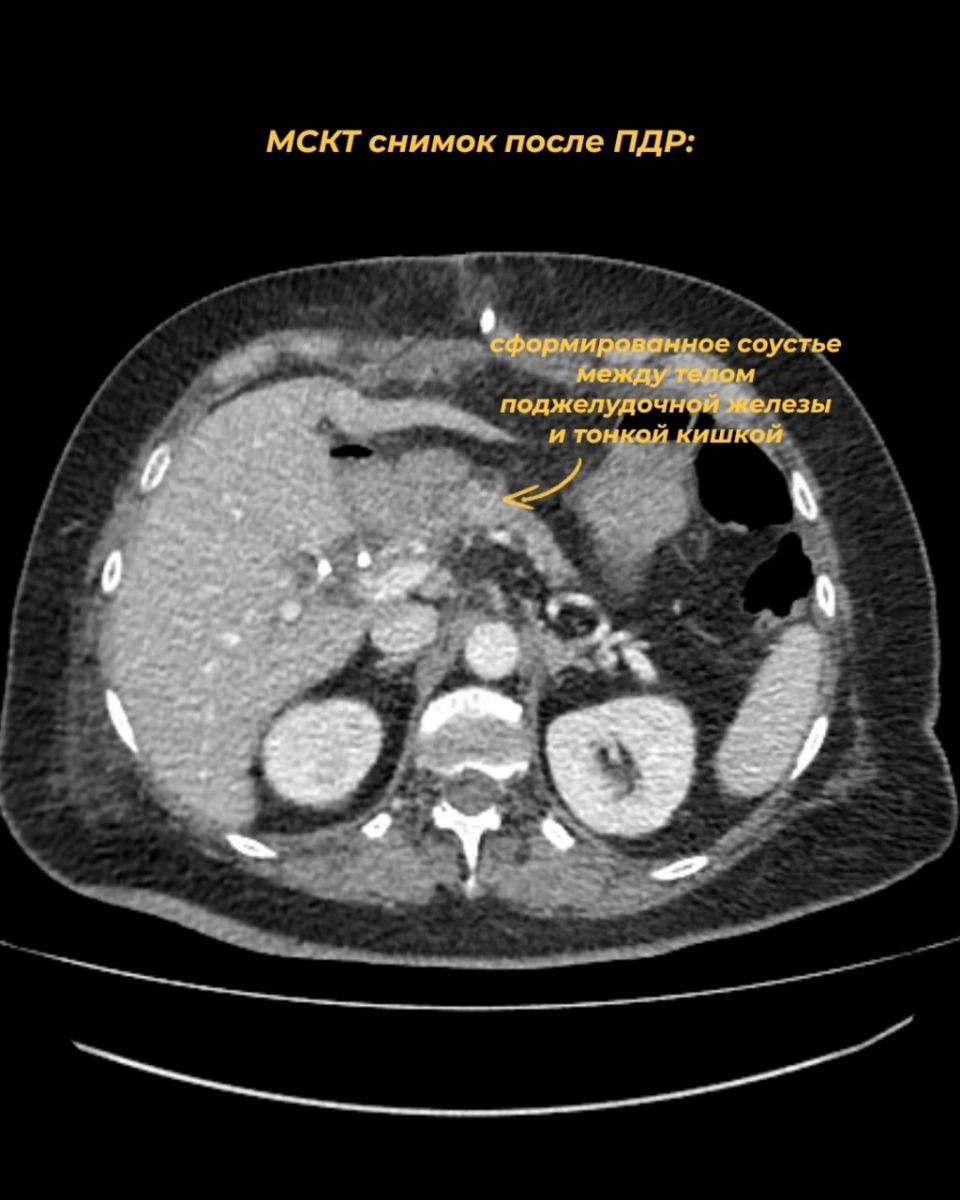

Операция длилась около 7 часов и прошла успешно без интраоперационных и послеоперационных осложнений. Это уже 15-е подобное вмешательство, проведенное в данном отделении с момента его создания. Пациентка была выписана домой к своим близким.